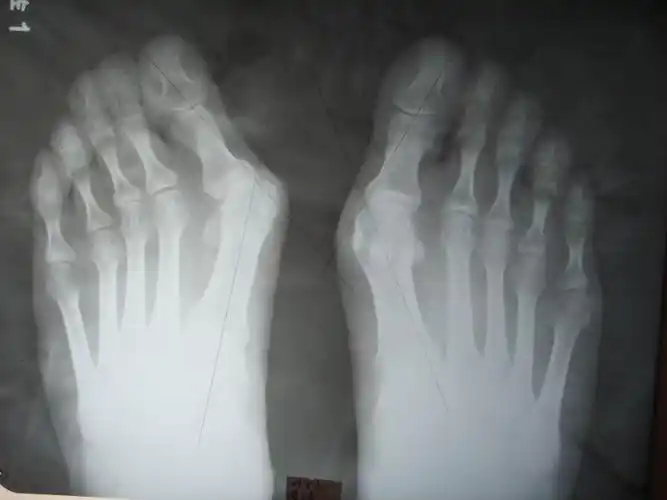

科普拇外翻俗称大脚骨

拇外翻图片与正常脚图片,大脚骨倾斜畸形不只是影响美观

正常足部和大脚骨对比